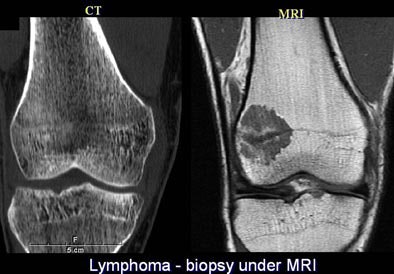

Finally, MRI beat CT in the case of another student, who came back from a ski trip with a knee injury. MDCT (1-mm reconstructions) showed only a vague sclerosis in the lateral femoral condyle, Gold said. On the other hand, proton-density fat-suppressed MRI image showed a marrow lesion in great detail. The lesion was lymphoma, biopsied under MRI to achieve better localization.